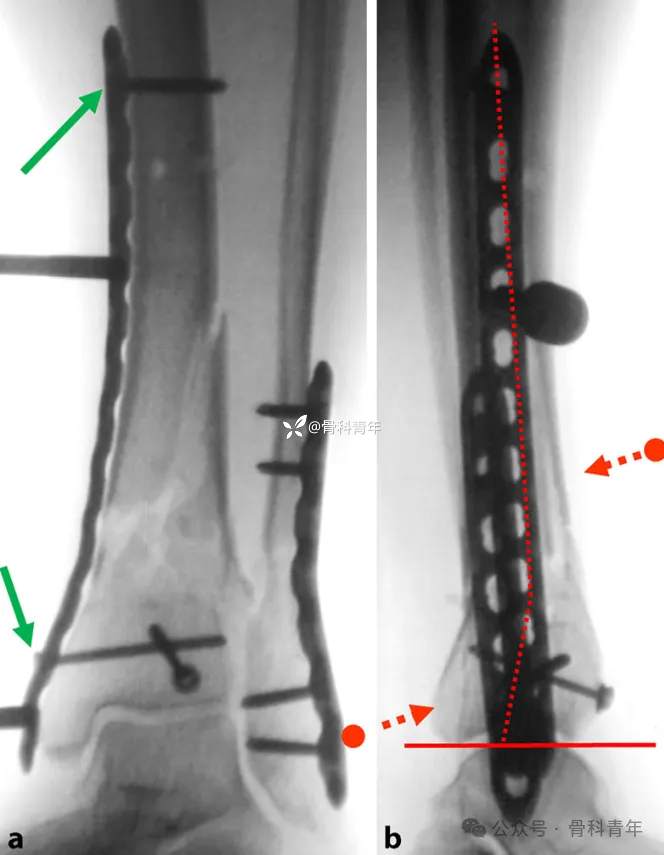

二、内翻/外翻畸形

明显的内外翻畸形通常合并腓骨/外踝骨折,对此类骨折,大多数医生选择优先固定简单骨折的外踝,恢复腓骨长度,作为胫骨复位的参考标准。胫骨内固定在内侧插入钢板后,先一枚螺钉固定远端,后在骨折线近端拧入锁定螺钉套筒,以套筒为操作杆上下移动,结合手法内外翻踝关节,以纠正内外翻畸形。

透视满意后,经上述锁定套筒置入螺钉即可。